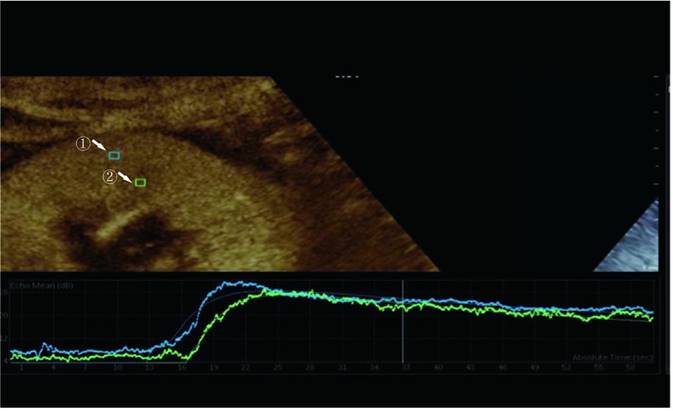

We examined prospective donor kidneys at the bedside using CEUS within 24 h before procurement. The patient's blood pressure and the use of vasoactive drugs during the examination were noted. Philips EPIQ7 ultrasonic diagnostic instrument with a c5-1 probe was used for a contrast-enhanced ultrasound examination. The blood pool contrast agent used in this study was SonoVue (Bracco, Milan, Italy), containing sulfur-hexafluoride microbubbles stabilized by a phospholipid shell. Some studies have confirmed the safety of SonoVue[12]. First, both the left and right sides of the kidneys were scanned longitudinally and transversely with conventional US. The renal size, echo, and cortical thickness were recorded. After a typical US examination of the potential donors, we positioned the ultrasonic probe along the kidney's long axis to disclose the renal hilus and maximum kidney area. Then, 1.0 mL of SonoVue was injected via the central venous catheter, followed immediately by an infusion of 5 mL of the saline solution. Image acquisition began at the start of the SonoVue injection and recorded the acquired images on the local hard disk drive in the form of DICOM. During CEUS, the primary gain, focus position, time gain compensation, and other preset parameters remain unchanged. The mechanical index was set at 0.07 (Figure 1).

Figure 1

Region of interest selected for quantitative analysis. Region ① is the ROI of the renal cortex. Region ② is the ROI of the renal medulla.

The perfusion software Sonolive was used to conduct a quantitative analysis of the images. The 'motion compensation' function was enabled to reduce respiration's impact during the analysis. A 4 ^ 2 mm square region of interest (ROI) was placed in the cortex and medulla of the kidney, excluding the interlobar and arcuate arteries (Figure 1). An ROI's signal intensity was measured, and a time-intensity curve (TIC) was generated. Using the following parameters, two TICs were generated for each kidney: rise time (RT), time to peak (TTP), peak intensity (PI), wash-in slope (WIS), the area under the curve (AUC), and mean transit time (MTT). The quantitative ROI parameters of the cortex and medulla were analyzed further.